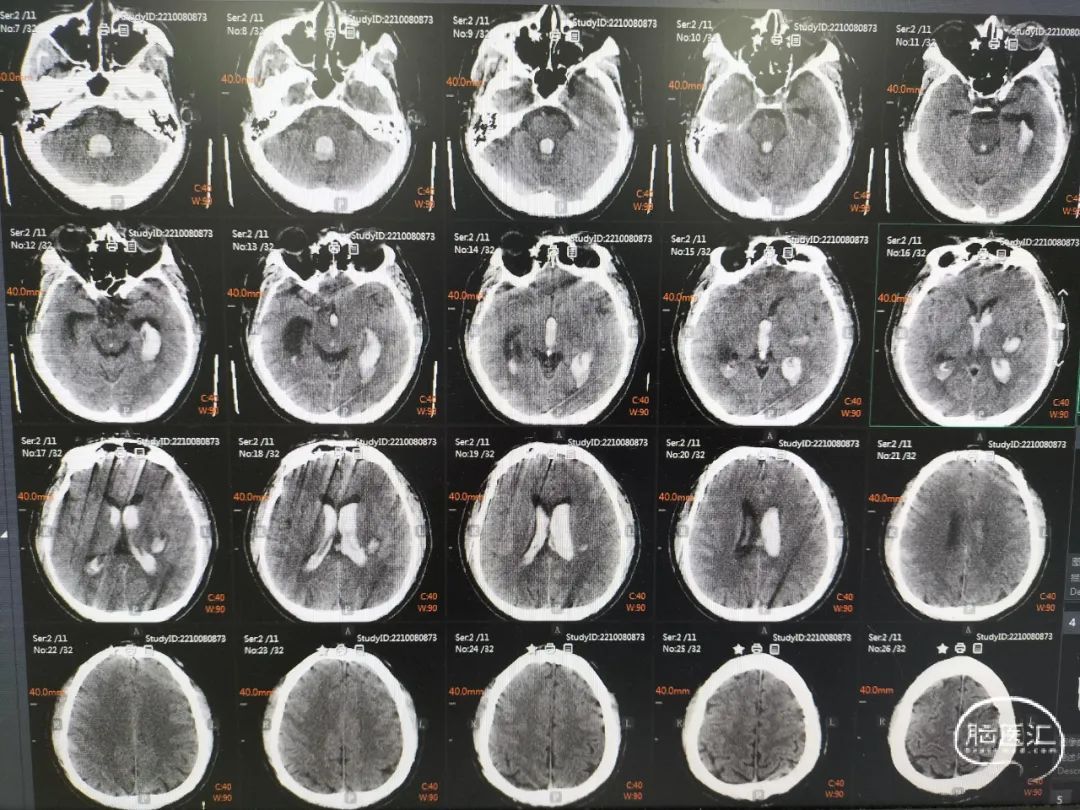

术前CT提示:脑内血肿,蛛网膜下腔出血。

术后第1天头颅CT提示:脑室系统积血较多,安排床旁锥颅脑室钻孔引流,尿激酶液化血肿。

术后一周头颅CT提示:脑室系统积血较前明显减少,更换腰大池置管引流。